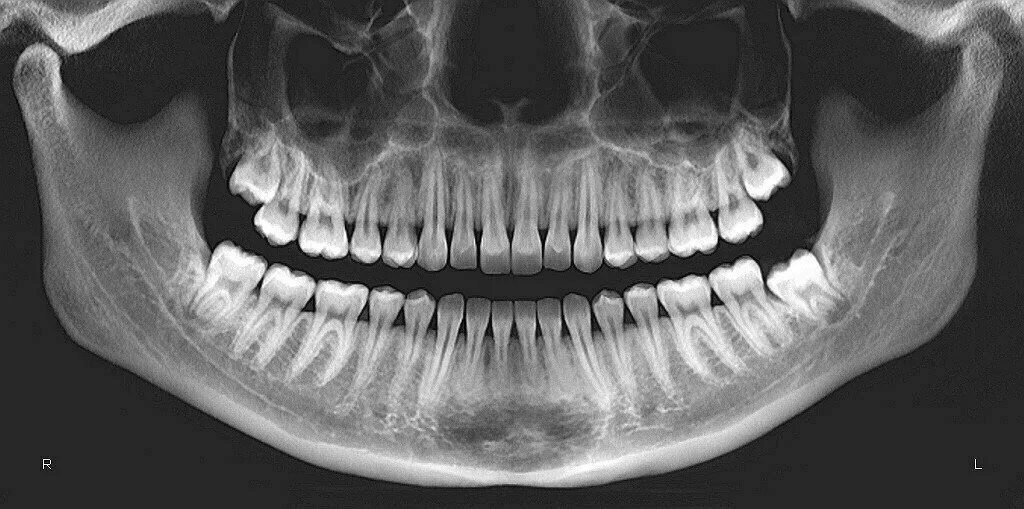

Снимок ротовой полости